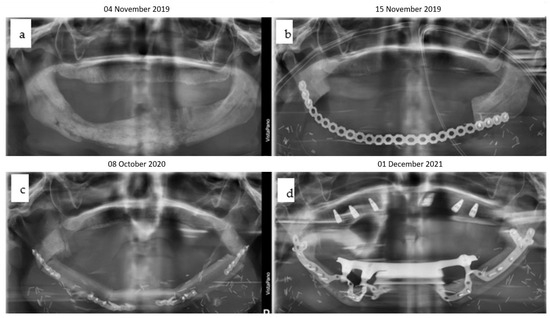

臨床解剖学に基づいたComprehensive Dental Surgery。臨床解剖学に基づいたComprehensive Dental Surgery。Exceptional Cases Demand Exceptional Personalized Solutions。すべての歯科医師のための臨床解剖学に基づいたComprehensive Dental Surgery折れや破れは無いかと思います。薬物治療学 改訂10版。。New Clinical Protocol to Evaluate Craniomaxillofacial。8000円→7500円にお値下げしました。8月14日さらにお値下げしました。ERでの創処置 縫合・治療のスタンダード 裁断済